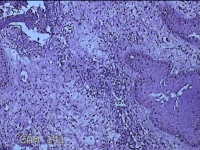

左侧会阴部结节

性别

女

年龄

43岁

临床诊断

皮肤良性肿瘤

一般病史

发现右侧会阴部结节3年余。

标本名称

大体所见

灰白粉红色带皮肤结节0.8x0.7x0.3cm一个,表面光滑,切开结节呈实性,切面灰白粉红色,质韧。

图3